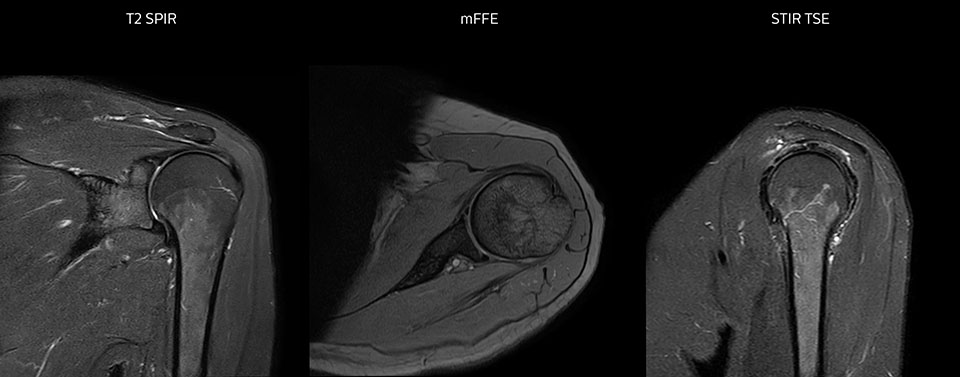

Shoulder MRI with high quality, large coverage

The Prodiva shoulder coil is very flexible and has large coverage, which makes good positioning easier, and that contributes to the superb image quality and high SNR that we get in our shoulder exams.

Scan time 2:55 min, FOV 160 mm,

acq voxels 0.55 x 0.83 x 3.0 mm.

Scan time 4:19 min, FOV 160 mm,

acq voxels 0.55 x 0.80 x 3.0 mm.

Scan time 2:50 min, FOV 160 mm,

acq voxels 0.70 x 0.99 x 3.0 mm.

Shoulder MRI with high quality, T2 SPIR

Shoulder MRI with high quality, mFFE

Shoulder MRI with high quality, STIR TSE